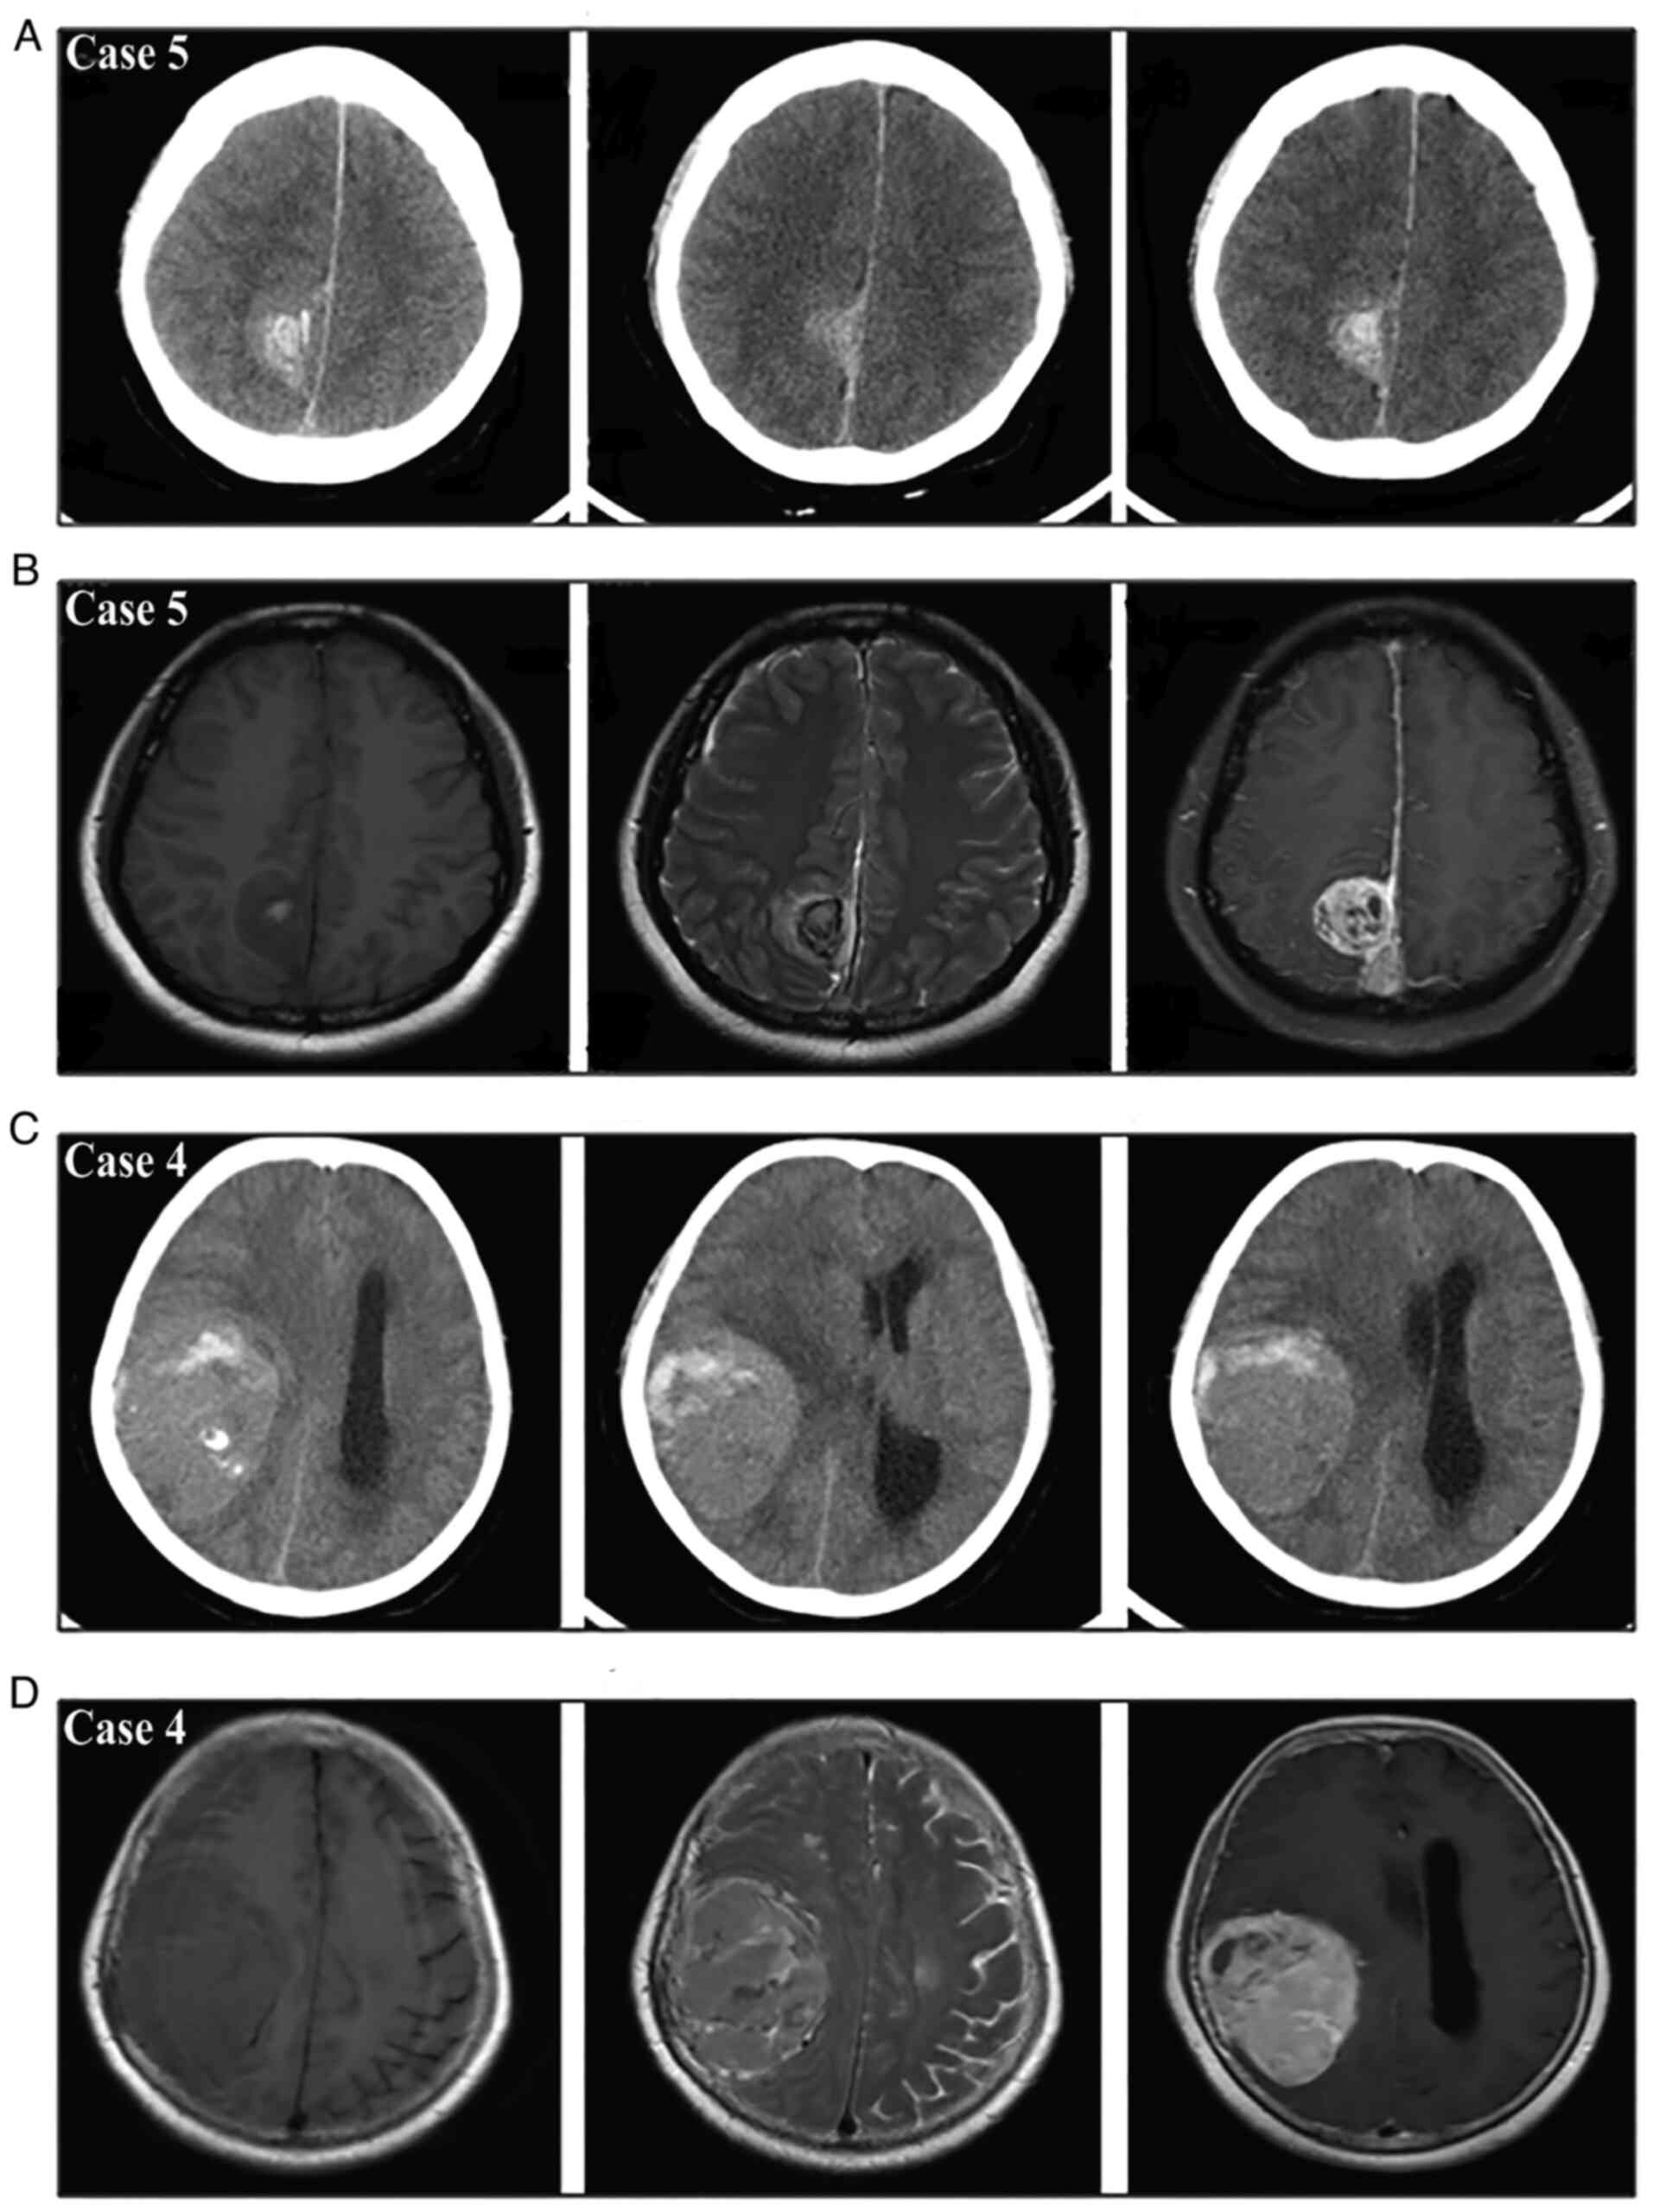

Meningiomas are the most common benign intracranial tumors and frequently present with a gradual onset of neurological deficits; conversely, their acute presentation with hemorrhagic onset appears to be a rare event. Nonetheless, as early surgical evacuation is the foundation of treatment, a timely diagnosis of this rare type of intracranial hemorrhage is necessary. The purpose of the present single‑center study was to investigate the radiological characteristics and propose a new bleeding classification for guiding the diagnosis and treatment. A total of 19 patients consecutively diagnosed with hemorrhagic meningioma were enrolled in this retrospective study. Intracranial extra‑axial mass, tumor‑associated hemorrhage and peritumoral brain edema were the three main radiological features of the hemorrhagic meningiomas. The site of tumor‑associated hemorrhage included the peritumoral space, subarachnoid space, subdural space, brain parenchyma and/or intratumor region. Based on the anatomical relationship between meningioma and hematoma, the spontaneous hemorrhage stemming from meningiomas was further summarized into three bleeding patterns involving purely intratumoral hemorrhage (type I), purely extratumoral hemorrhage (type II) and combined intra/extratumoral hemorrhage (type III); furthermore, the type III hemorrhage usually came from type I bleeding that extended into the surrounding regions. The symptoms in type I patients were generally mild and early surgery was performed following adequate preoperative evaluations. The symptoms in type II patients were mild in certain cases and moderate to severe in others, so early or emergency surgery was chosen according to the clinical status of the patient. Almost all type III patients had moderate to severe symptoms and these patients usually required emergency surgery. In addition, patients with different bleeding types may have different pathological mechanisms underlying the tumor bleeding. Apart from being convenient for diagnosis, this concise and practical bleeding classification may aid in the selection of the treatment strategy and facilitate the understanding of the associated mechanisms.

Figure 1

Figure 2

Figure 3

Figure 4

Figure 5

Figure 6

Figure 7

Figure 8

Figure 9